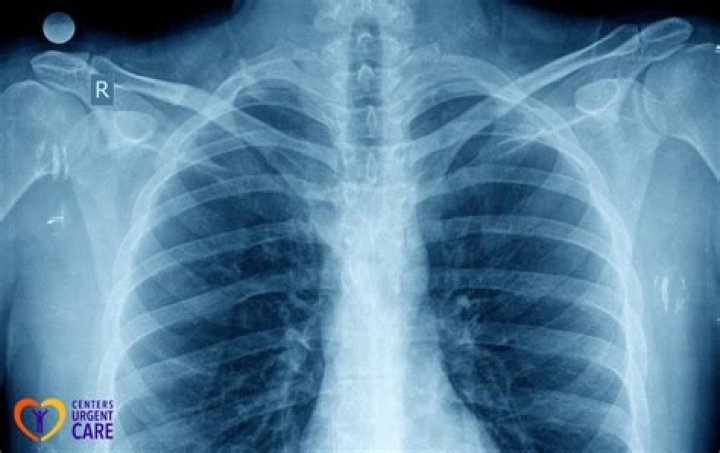

Do organs show up on X-rays?

X-rays use beams of energy that pass through body tissues onto a special film and make a picture. They show pictures of your internal tissues, bones, and organs. Bone and metal show up as white on X-rays. X-rays of the belly may be done to check the area for causes of abdominal pain.